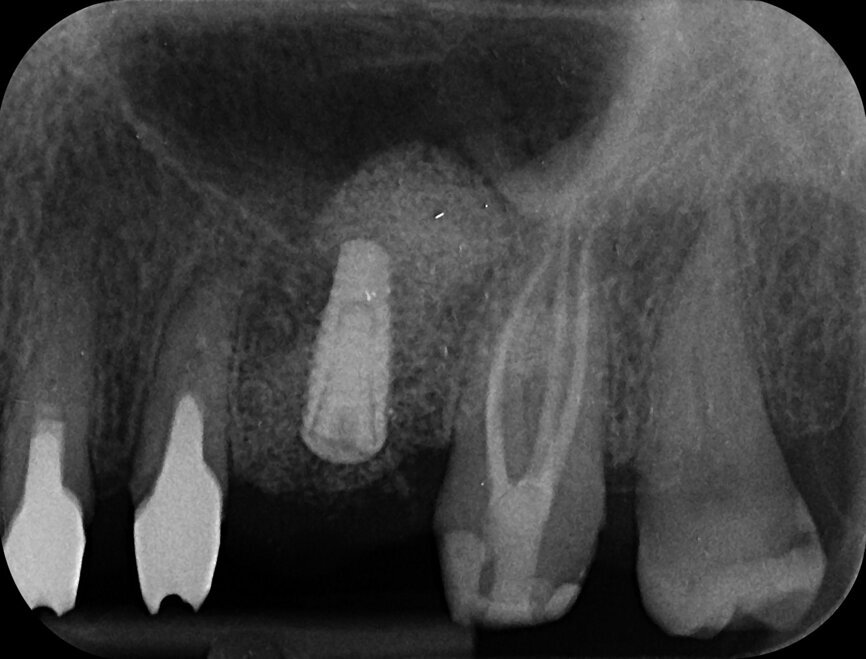

The patient who is the focus of our discussion came to our office reporting intense pain in response to hot and cold stimuli in the left maxilla (Fig. 1). He described the pain as being spontaneous at times and that in order for it to subside administration of anti-inflammatory medication was required. Upon examination, an accurate diagnosis was established of symptomatic irreversible pulpitis affecting tooth #27. The patient had had the tooth prepared for a crown sometime in the last 60 days (Fig. 2), but unfortunately the treatment was not completed for unknown reasons. Caries seemed to be absent; therefore, a minimally invasive approach was planned. Most likely, the pathology was caused by either trauma or an iatrogenic event.

After isolation of the tooth (Fig. 3), an access cavity was created using high-speed diamond burs and ultrasonic tips (Figs. 4–8). Pre-flaring in the coronal and middle thirds was done with the HyFlex EDM 25 instrument (at a torque of 4 Ncm and a speed of 500 rpm). It is a proven fact that pre-flaring allows an increase in the instrument size that binds in the root canal, irrespective of the discrepancy between the size of the file and anatomical diameter. [19–21] Afterwards, canal scouting was performed using an ISO size 10 stainless-steel K-file up to working length. Upon establishing the working length, with the help of an apex locator, the 10/05 EDM file (glide path file) was used up to working length (at a torque of 3 Ncm and a speed of 300 rpm). Subsequently before finishing the preparation with the 25 EDM file, the 20/05 EDM (preparation file) was used to full working length (at a torque of 3 Ncm and a speed of 400 rpm). At this point, the working length was confirmed again with an ISO size 20 NiTi K-file. Root canal shaping was completed with the 25 EDM file, which was inserted to full working length (at a torque of 3 Ncm and a speed of 400 rpm; Figs. 9–12).